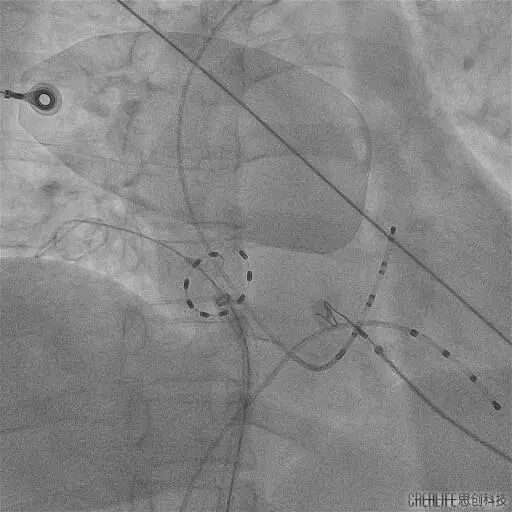

今年60岁的崔伯伯(化名)和59岁的张阿姨(化名)因房颤发作频繁,极大的影响日常生活,甚至呈焦虑状态,遂就诊武汉亚洲心脏病医院;在完善心脏彩超、食道超声及左房CT等一系列检查后,张劲林主任和韩宏伟主任经过充分的评估和与患者及家属的知情确认后,选择脉冲电场消融术为其治疗,该项技术以其高安全性、高效性和微创性,为房颤患者带来了更为优质的治疗选择。术中使用脉冲电场消融导管分别在四根肺静脉进行消融,每根肺静脉口内定位4个位置,前庭定位6-8个位置,逐次放电(电压1500V) 。每根肺静脉首次放电,肺静脉电位振幅即可明显下降至消失,四根肺静脉均完成肺静脉电隔离。

PS导管通过外鞘送入左心房,在二维引导下到达目标肺静脉,在导丝指引下调整导管成环进入肺静脉,使环形电极贴靠肺静脉口/前庭。

观察电极形变并明确电位,确认贴靠良好后依次对每个每支静脉进行口部4次+前庭6-8次的脉冲消融,对上腔静脉补充4次消融,完成四根肺静脉(PVI)和上腔静脉的环形隔离。

PS导管行SVC消融